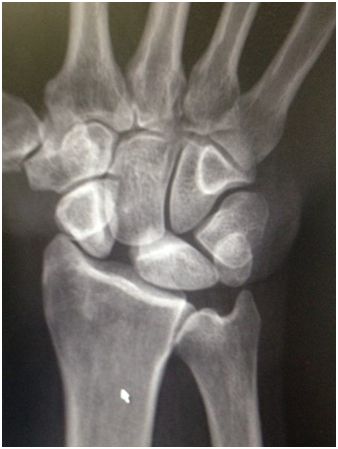

These injuries are relatively common and are either frequently missed or underestimated. The scapholunate ligament (SLL) is a ligament in the central aspect of the wrist and is an important stabiliser of the wrist . It is therefore the equivalent of the “Cruciate” ligament of ACL of the knee. If it is seriously injured the patient can develop pain on load bearing esp doing press ups or lifting objects. Certain everyday tasks can become painful if seriously injured. If the injury is neglected, premature arthritis and collapse of the wrist may occur in certain situations.

After scaphoid fractures, the SLL is probably the most commonly missed injury and this can have potentially detrimental effects for the patient.

An early MRI scan is required to make a prompt diagnosis. If diagnosed early (within 6 weeks) a repair of the ligament is possible. When diagnosed later, reconstruction using tendon graft is often required. The latter is more complex surgery and therefore an early diagnosis is recommended.